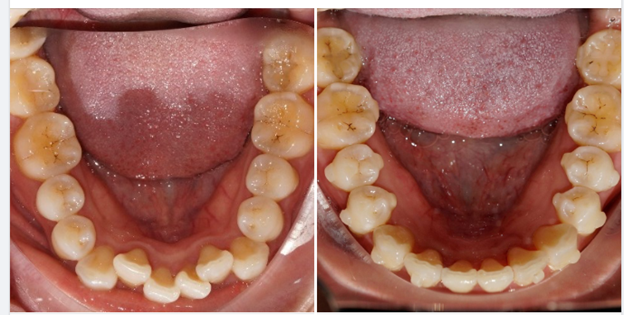

2. Biểu hiện xô lệch răng do răng khôn

Một số dấu hiệu thường gặp gồm:

- Răng cửa hàm dưới chen chúc, xoay nhẹ

- Các răng đang đều dần trở nên khấp khểnh

- Khớp cắn thay đổi, cảm giác cộm khi cắn chặt

- Thức ăn dễ mắc kẹt giữa các răng

Nhiều người sau khi niềng răng xong vài năm bị tái lệch cung răng, nguyên nhân thường liên quan đến răng khôn chưa được xử lý.